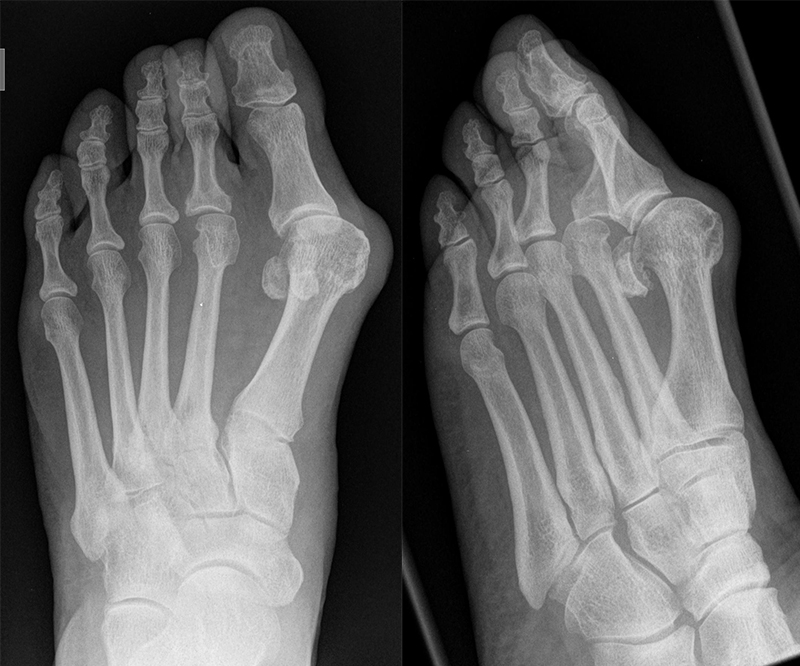

An erster Stelle der bildgebenden Diagnostik steht die konventionelle Röntgendiagnostik. Der betroffene Fuß wird dabei unter Belastung in 3 Ebenen dargestellt. Beurteilt werden der Intermetatarsale-I-Winkel (IM-Winkel), der Hallux valgus Winkel (HV-Winkel), die Lage der Sesambeine, der Arthrosegrad im MTP I Gelenk und ein mögliches plantares Klaffen „gapping“ im Tarsometatarsale-I Gelenk als Hinweis auf eine Gelenkinstabilität. Neben der reinen Beurteilung des Hallux valgus sollten immer auch die Kleinzehen beurteilt werden.

Ziel des Eingriffs ist es, den Intermetatarsalwinkel auf einen Wert von 3-8° zu korrigieren. Hierzu wird der distale Anteil des Os metatarsale I nach lateral geschwenkt und auf den Sesambeinkomplex zurückgeschoben. Ein zentriert über den Sesambeinen stehender Metatarsalekopf ist ein guter Indikator für eine adäquate Korrektur. Die Korrektur der Fehlstellung sollte knöchern erfolgen. Ein späteres „Geradeziehen“ der Großzehe durch eine Cerclage fibreux hat eine hohes Rezidivrisiko und führt häufig zu einem steifen Großzehengrundgelenk. Bei guter knöcherner Korrektur kann die Gelenkkapsel beim Wundverschluss unter Resektion der überschüssigen Kapselanteile spannungsfrei verschlossen werden. Nach dem Kapselverschluss sollte eine freie Beweglichkeit im Großzehengrundgelenk vorhanden sein.

Sowohl für die Scarf-Osteotomie 4232425, als auch für die Ludloff-Osteotomie 52627 sind in der Literatur gute Resultate dokumentiert. Choi et al. 28 berichteten in einer prospektiven Fallkontrollstudie über eine sehr gute Korrektur des Hallux valgus Winkels von 29° auf 10,6°, des Intermetatarsalwinkels von 13,6° auf 5,6° bei guter Rezentrierung der Sesambeine. Die Gesamtkomplikationsrate lag bei 15%. Eine Hallux varus Fehlstellung entwickelte sich in 4%, eine progrediente Arthrose führte in 4% zur Notwendigkeit einer Arthrodese.

In einer Metaanalyse verglich die Autorengruppe um Schuh et al. 29 die Ergebnisse verschiedener Ostetomieformen zur Korrektur des Hallux valgus. Die Gesamtkomplikationsrate bei der Ludloff-Osteotomie lag bei 23,7%. Die Korrektur des Hallux valgus Winkels wurde mit 23,3° angegeben, die Korrektur des Intermetatarsalwinkels lag bei 9,2°.